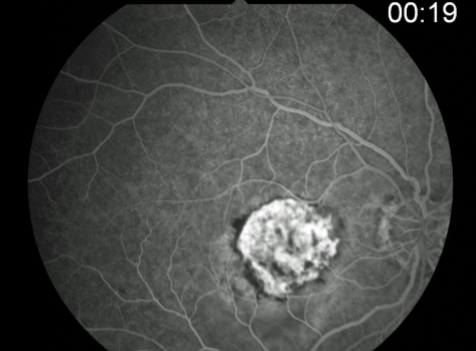

classic CNV/Gass type 2

CNVM

well defined hyperfluorescence

cartwheel or sea fan appearance

thought to break through RPE & staying sub-retinal

type 2 MNV

MNV is now b/t neurosensory retina & RPE making the IVFA more obvious & well defined

IVFA shows lacy, well-group area of neovascularization

hyperfluorescent early in study

late leakage

lacy early fill of the MNV during the choroidal & arterial filling phase

may have hypofluorescence corresponding to RPE hyperpigmentation & blood in the outline of the MNV

classic CNV

type 2 MNV

MNV type 2

MNV type 2

MNV type 2

MNV type 2

MNV type 2